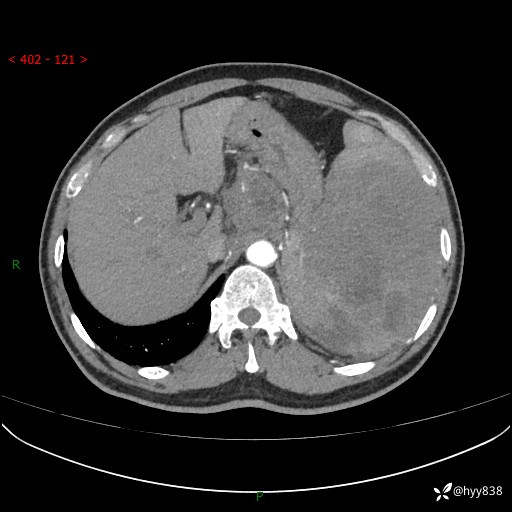

上腹部CT平扫

增强(动脉期+静脉期)